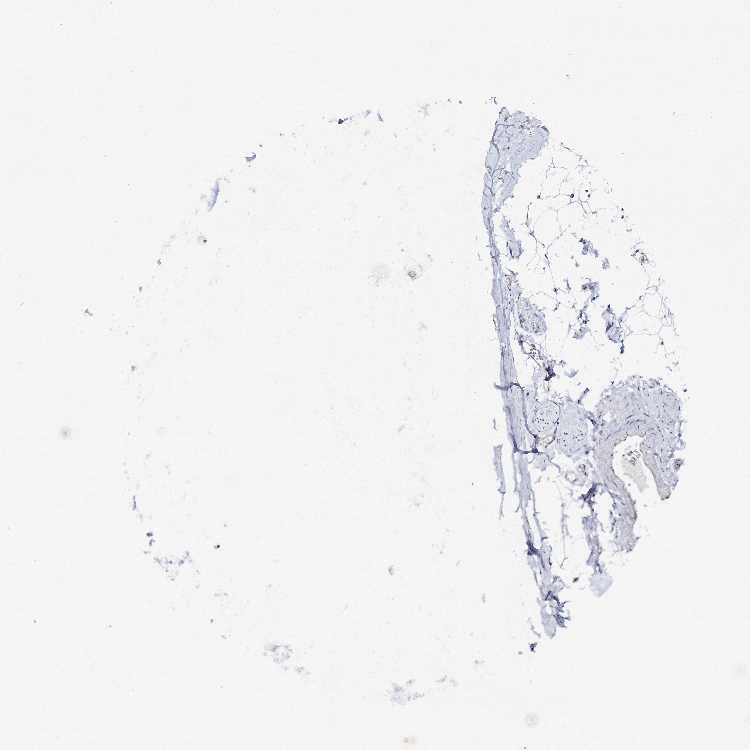

SOFT TISSUE 2 - Antibody stainingi

Antibody staining in the annotated cell types in the current human tissue is reported as not detected, low, medium, or high, based on conventional immunohistochemistry profiling in selected tissues. This score is based on the combination of the staining intensity and fraction of stained cells.

Each image is clickable and will lead to virtual microscopy that enables deeper exploration of all samples and also displays staining intensity scores, fraction scores and subcellular localization as well as patient and tissue information for each sample.

Antibody HPA034631Antibody HPA071347Antibody CAB033265Antibody CAB037325

Fibroblasts HighNot detectedNot detectedNot detected

Peripheral nerve -Not detected--